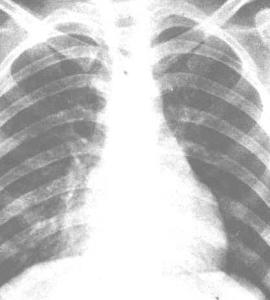

腺病毒肺炎多发群体,腺病毒一般通过呼吸道传染。在集体儿童机构中往往同时发生腺病毒上呼吸道感染及肺炎。人群血清学研究说明,生后最初数月常存留从母体传递的腺病毒特异抗体,此后一直到2岁抗体缺乏,2岁以后才逐渐增加。这与腺病毒肺炎80%发生在7~24月婴幼儿的临床观察完全符合。值得注意的是当地各年龄组易感人群数量越多,发生腺病毒呼吸道感染的人数就多,而婴幼儿发生腺病毒肺炎的机会也越大。腺病毒肺炎在中国北方多见于冬、春两季,夏、秋季仅偶见,在广州的高流行年则多见于秋季。这类肺炎在北京约占病毒性肺炎的20%~30%。